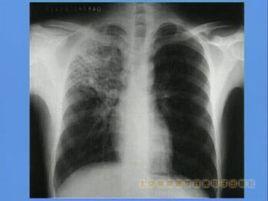

大葉性乾酪性肺炎多見於嬰幼兒,小葉性者則多見於較大兒童。前者起病多較急,有高熱和嚴重中毒症狀,後者可較緩,有長期低熱和慢性中毒症狀。多有咳嗽、吐痰甚至咯血。肺部可聽到支氣管呼吸音或管狀呼吸音,及大量響亮中、小水泡音。X線攝片在大葉性乾酪性肺炎可見大片濃密陰影,內有透亮區;在小葉性乾酪性肺炎可見兩肺散在密度不均之團塊狀陰影,內有蜂窩狀透亮區或大小不等之無壁空洞。血象可見:中性多形核粒細胞高度增多及核左移現象,血沉加速,痰及胃液中可找到大量結核桿菌。鑑別診斷應與大葉性肺炎、支氣管肺炎或肺膿腫相鑑別。本型病程嚴重,預後不佳。但如能及時積極進行抗結核藥物治療,多數病例可吸收好轉,後廣泛鈣化而治癒;部分患兒可轉變為慢性纖維空洞型肺結核;少數就診過晚可很快死亡,此即所謂"奔馬癆",多見於青春期少女。